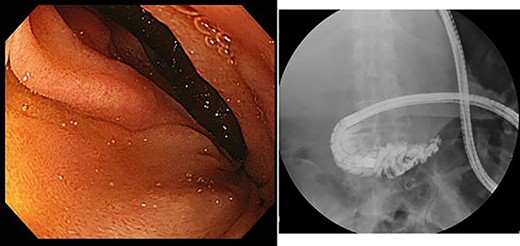

Upper gastrointestinal endoscopy showed severe duodenal stenosis due to compression from outside of the wall, which was the cause of gastric pain and anorexia (Fig. 3).

Upper gastrointestinal endoscopy showed severe stenosis of the duodenum.

However, during hospitalization, the patient developed dehydration, acute renal failure, electrolyte imbalance and impaired consciousness. C-reactive protein level was elevated (9.61 mg/dL), indicating intracystic infection. As emergency treatment, percutaneous puncture drainage of the cyst was performed to decompress the stomach and duodenum (Fig. 4).

Percutaneous puncture drainage improved the obstruction of duodenum.